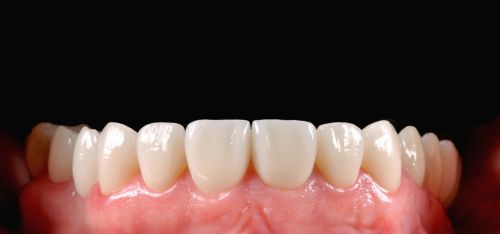

Wykonana praca protetyczna:

- licówki pełnoceramiczne w odcinku przednim zębów górnych

- korony pełnoceramiczne na zęby własne zarówno w łuku dolnym i górnym

- korony na implantach braków zębów